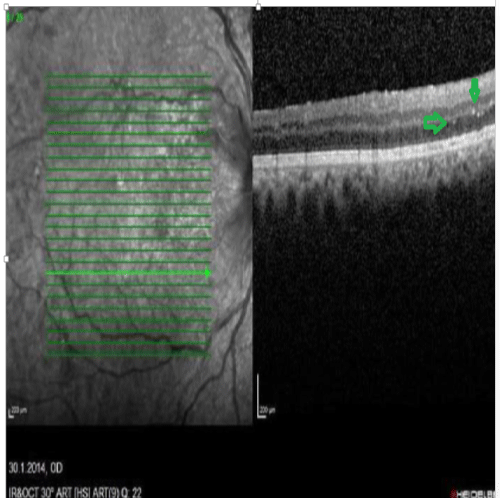

In 26 patients, our retina exams with FAF and OCT helped us see abnormal depositions mostly in the outer plexiform , ganglion and nerve fiber layers of the retina (Figures 1-4). The depositions were dot shaped and had different sizes.

Figure 1: OCT image. Lesion in the nerve fiber and ganglion layers

These accumulations were mostly in the perimacular and perivascular areas. We believe that these plauqes are related to neurodegenerative disease. In the patients who used curcumin, it was possible to detect patchy hypofluorescent areas.